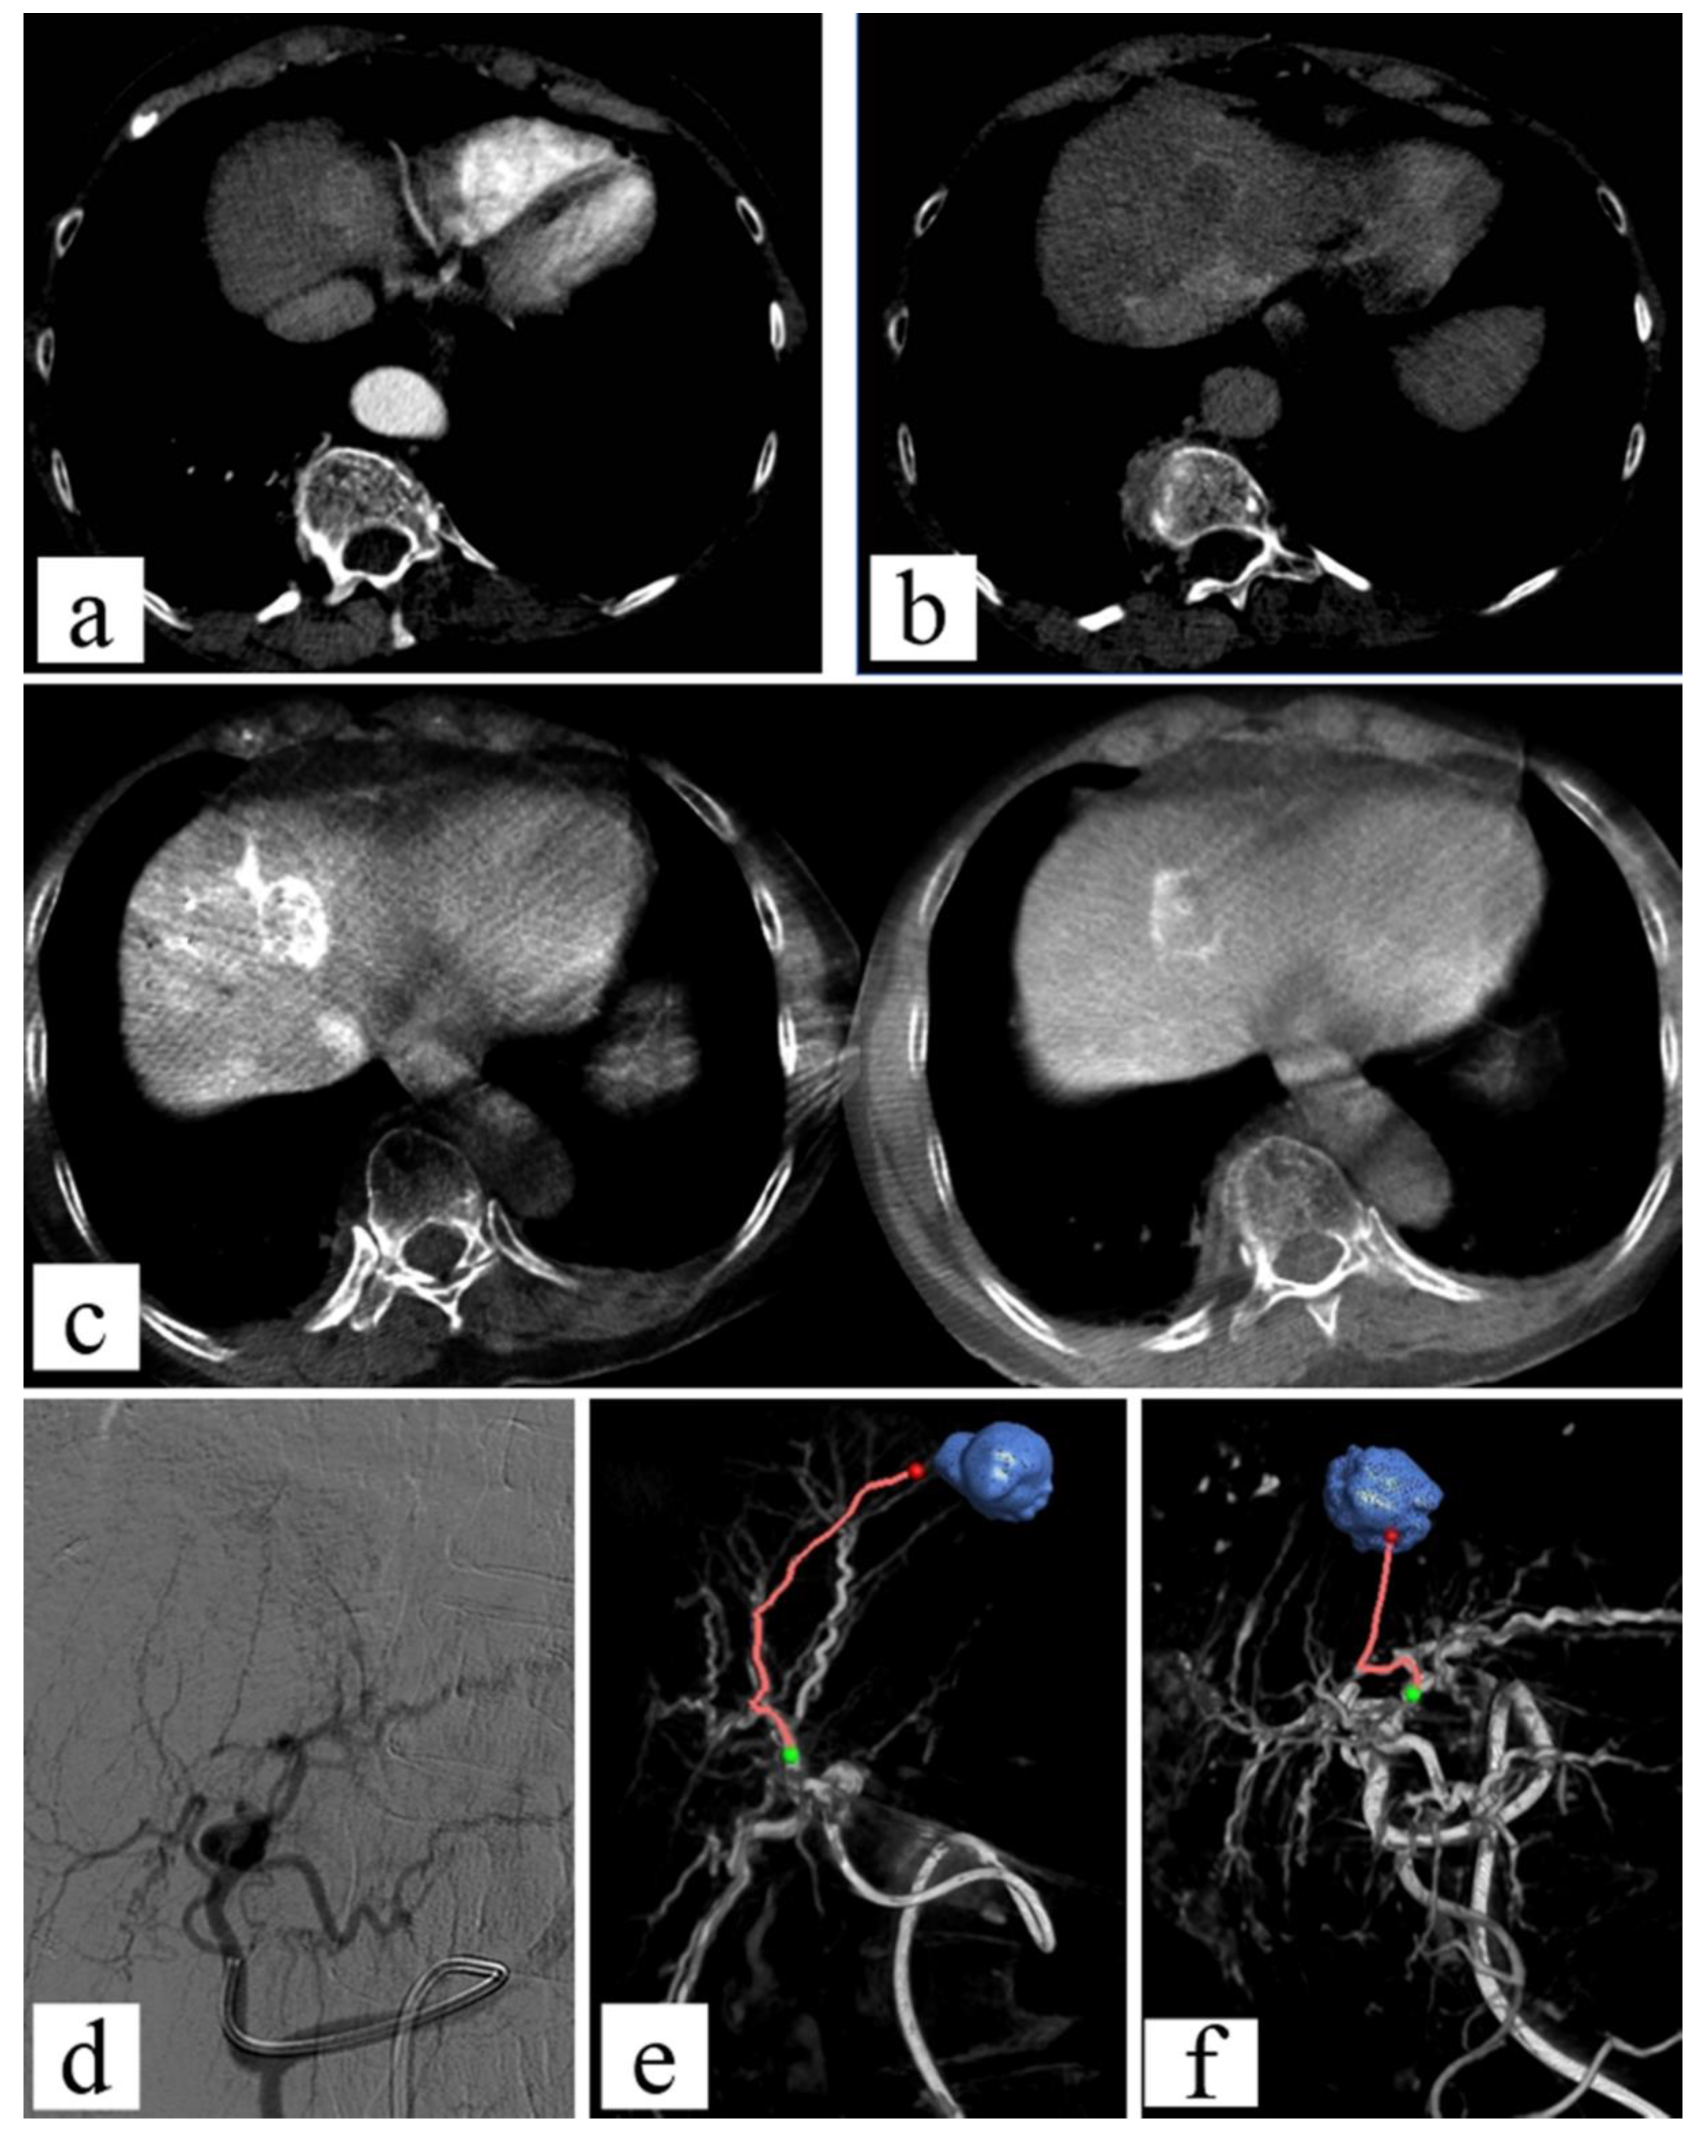

- Taiji, R.; Lin, E.Y.; Lin, Y.-M.; Yevich, S.; Avritscher, R.; Sheth, R.A.; Ruiz, J.R.; Jones, A.K.; Chintalapani, G.; Nishiofuku, H.; et al. Combined Angio-CT Systems: A Roadmap Tool for Precision Therapy in Interventional Oncology. Radiol. Imaging Cancer 2021, 3, e210039. [Google Scholar] [CrossRef]

- Lionberg, A.; Nijhawan, K.; Navuluri, R.; Zangan, S.; Van Ha, T.; Funaki, B.; Ahmed, O. Hybrid Angiography-CT for Transarterial Radioembolization: A Pictorial Essay. Abdom. Radiol. 2021, 46, 2850–2854. [Google Scholar] [CrossRef] [PubMed]

- Yuan, H.; Liu, F.; Li, X.; Guan, Y.; Wang, M. Angio-CT-Guided Transarterial Chemoembolization Immediately in Combination with Radiofrequency Ablation for Large Hepatocellular Carcinoma. Acad. Radiol. 2019, 26, 224–231. [Google Scholar] [CrossRef] [Green Version]

- Li, J.; Li, Z.; Jiao, D.-C.; Si, G.; Zhou, X.; Li, Y.; Liu, J.; Han, X. Clinical Outcomes After Selective Renal Artery Embolization Combined With DynaCT-Guided Microwave Ablation for T1a Renal-Cell Carcinoma: Case Series. Clin. Genitourin. Cancer 2021, 19, e1–e5. [Google Scholar] [CrossRef] [PubMed]

- Li, Z.; Jiao, D.; Han, X.; Si, G.; Li, Y.; Liu, J.; Xu, Y.; Zheng, B.; Zhang, X. Transcatheter Arterial Chemoembolization Combined with Simultaneous DynaCT-Guided Microwave Ablation in the Treatment of Small Hepatocellular Carcinoma. Cancer Imaging 2020, 20, 13. [Google Scholar] [CrossRef] [Green Version]